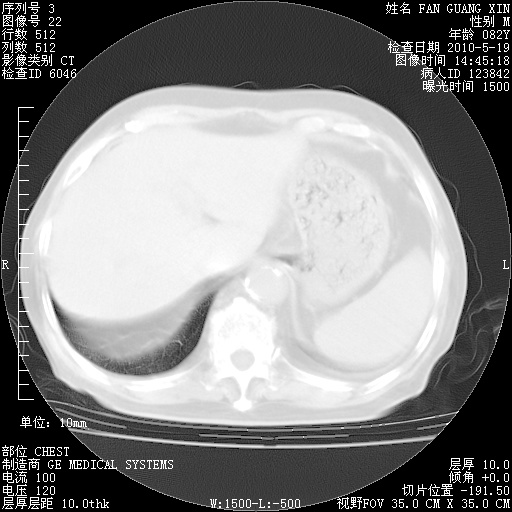

可改为口服强的松40-50mg/d治疗,若病情仍稳定,胸部阴影不再吸收可逐渐减量